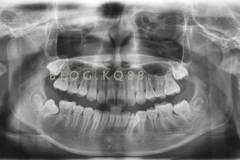

下面這個小患者就存在需早期矯正的問題。通過早期矯正,在不長的時間內(nèi)就達(dá)到極為明顯的療效。她的情況如果等到牙齒替換完畢后再解決,矯治的難度則會非常大。

早期矯正之前